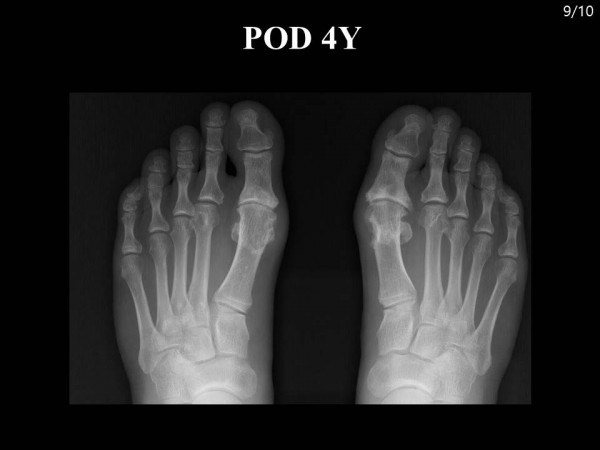

논문 및 학술활동 족부 양측 족부의 여러 부위에 동통성 종괴를 호소하는 58세 남자 환자 case report 20.08.24 15:33 1,798 양측 족부의 여러 부위에 동통성 종괴를 호소하는 58세 남자 환자 case report : 2018 대한족부족관절학회 춘계학술대회 양측 발 통풍성 결절로 내원한 환자 증례보고 이전글 Subtalar Arthroscopy and Posterior Endoscopy (거골하 관절경술 및 후방 내시경술) 20.08.24 다음글 족저 근막 파열 환자에서의 초음파 소견 20.08.24 목록